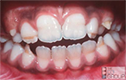

At case level, a typical Molar Hypomin mouth may have:

- from one- to all four Hypomin molars of any type (obligatory)*, plus/minus...

- one or more Hypomin adult incisors, generally less-affected than the molars (optional)

- *note the "sporadic presentation" of demarcated opacities (affecting different molars to different degrees) is a key diagnostic feature of Molar Hypomin